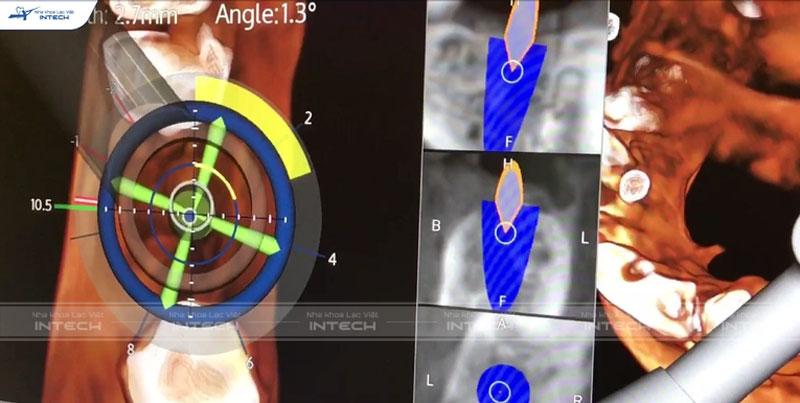

Các thông số quan trọng như khoảng cách từ bờ xương ổ răng tới ống răng dưới, đường đi của ống răng cần được đo đạc một cách chính xác thông qua thiết bị tầm soát hình ảnh CT Cone Beam. Nhờ đó bác sĩ có thể lựa chọn trụ Implant với đường kính, chiều dài phù hợp tại từng vị trí cụ thể.

Tại Nha khoa Lạc Việt Intech ứng dụng công nghệ trồng răng Safe Tech giúp hỗ trợ bác sĩ trong việc lên phác đồ điều trị an toàn, thành công tới 99,8%.

Công nghệ trồng răng Implant Safe Tech

Dữ liệu từ hệ thống máy Scan trong miệng và CT Cone Beam được tích hợp dựa trên công nghệ Smart Tech giúp xử lý, tạo hình ảnh giả lập 3D. Nhờ đó bác sĩ có thể quan sát tổng thể cấu trúc xương hàm, mật độ xương, hệ thống xoang hàm, dây thần kinh… Từ đó đưa ra phác đồ điều trị an toàn, loại bỏ những nguy cơ biến chứng có thể xảy ra.